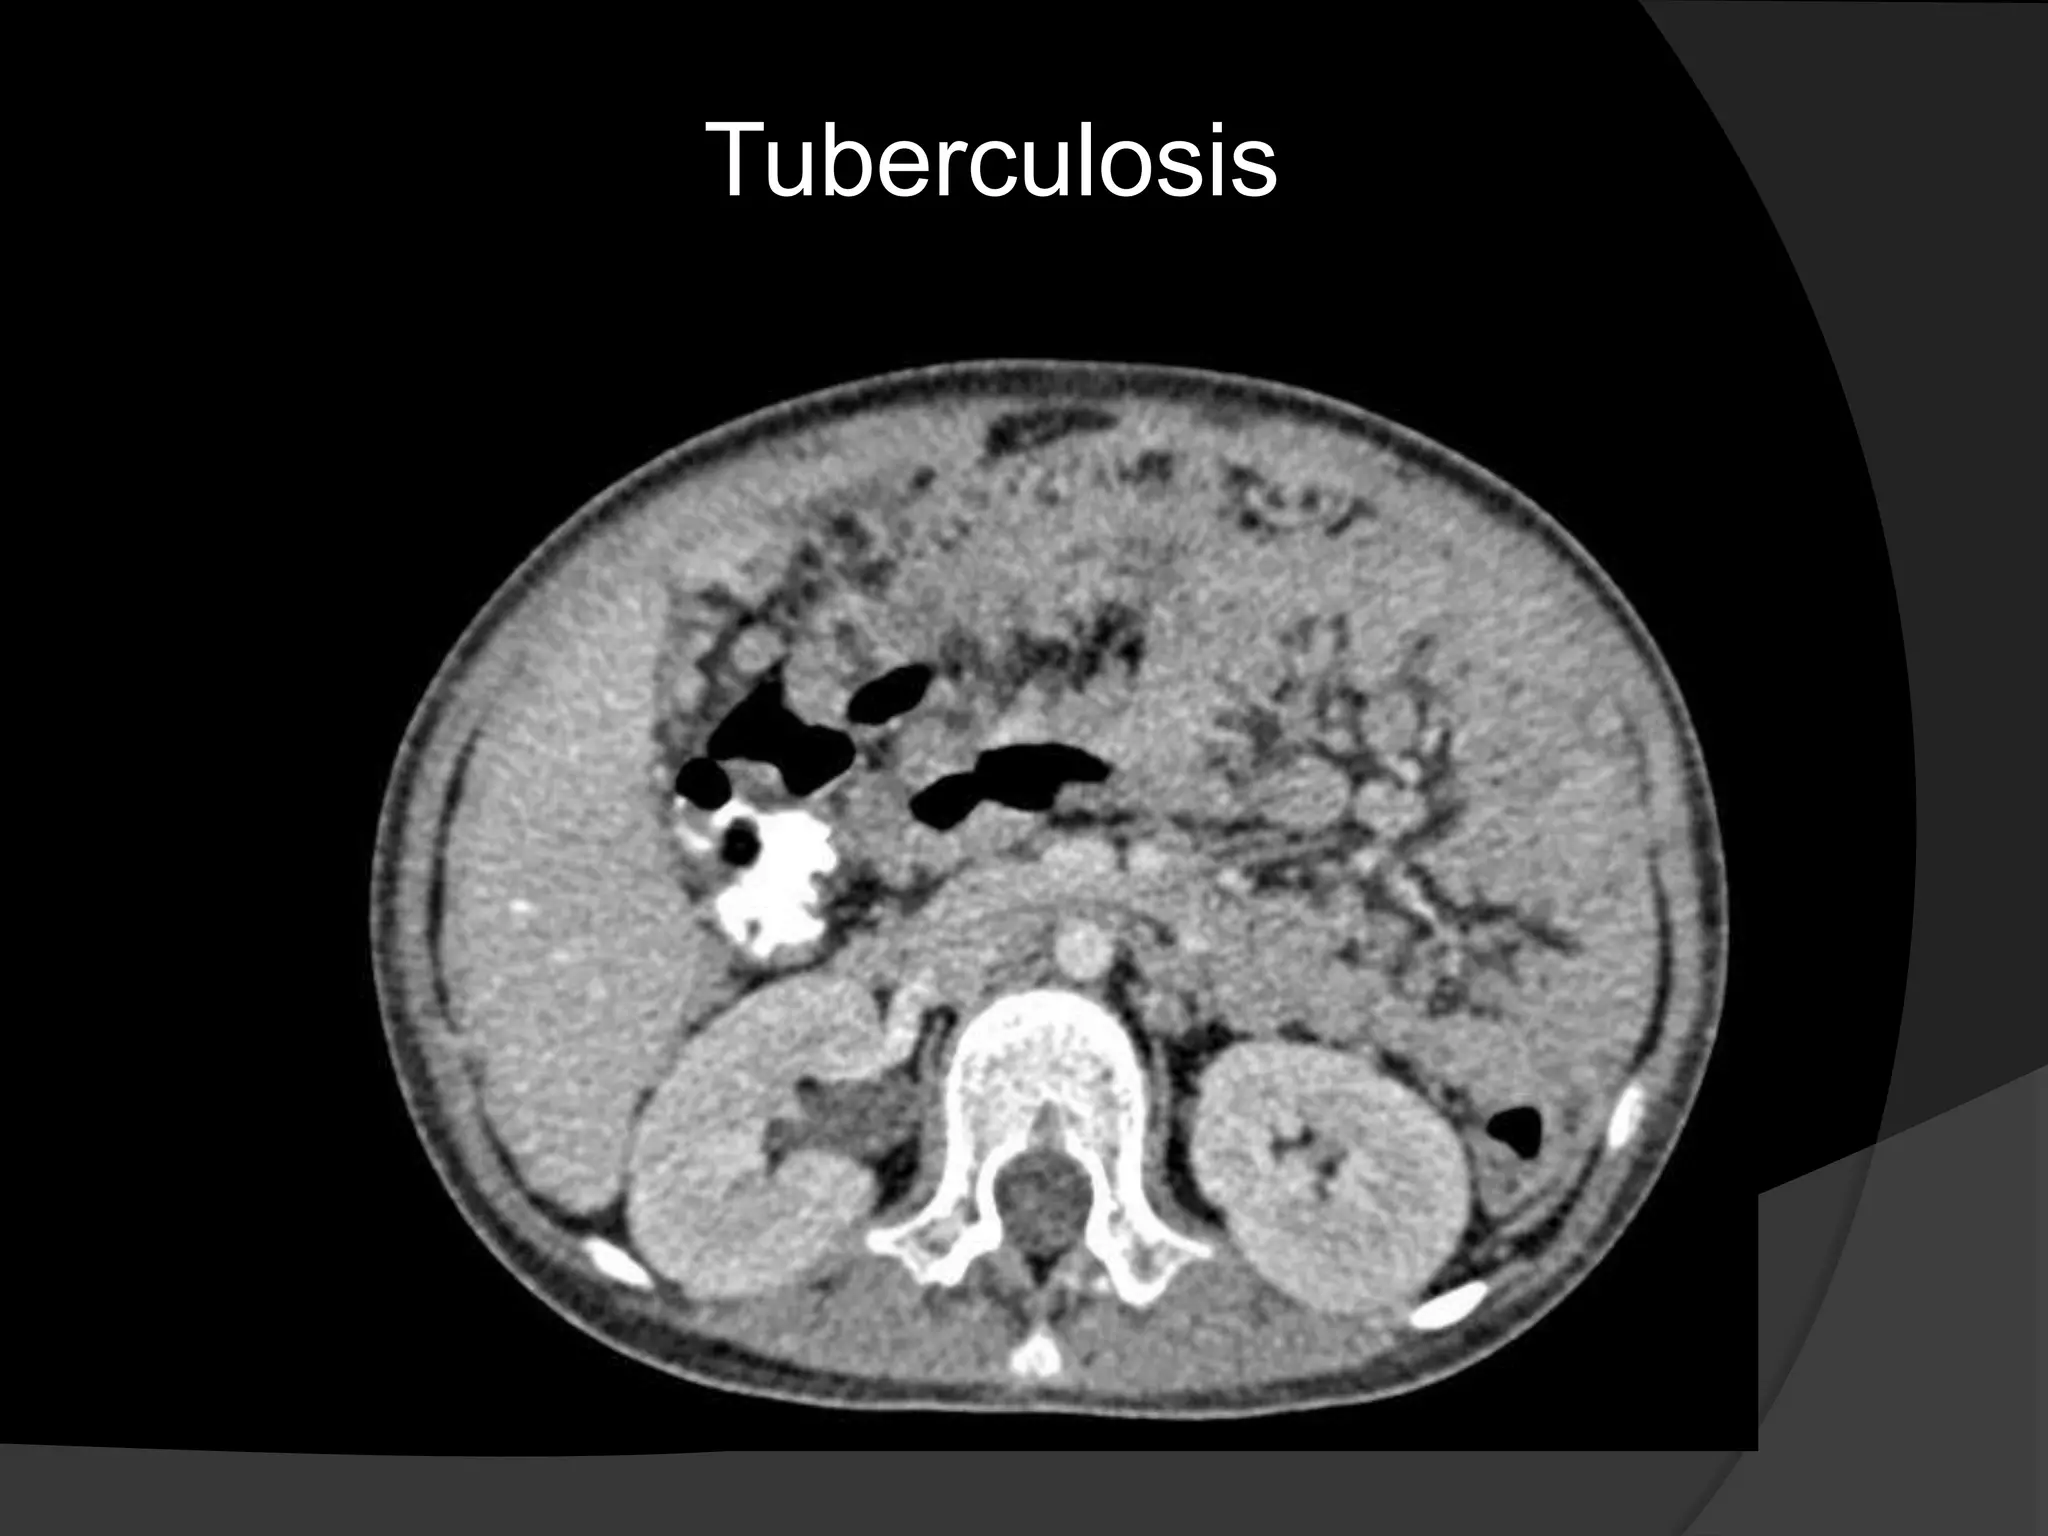

Tuberculosis

Usually there is accompanying abnormality of the terminal ileum and lymphadenopathy.

The lymph nodes most often are of low attenuation (caseated).